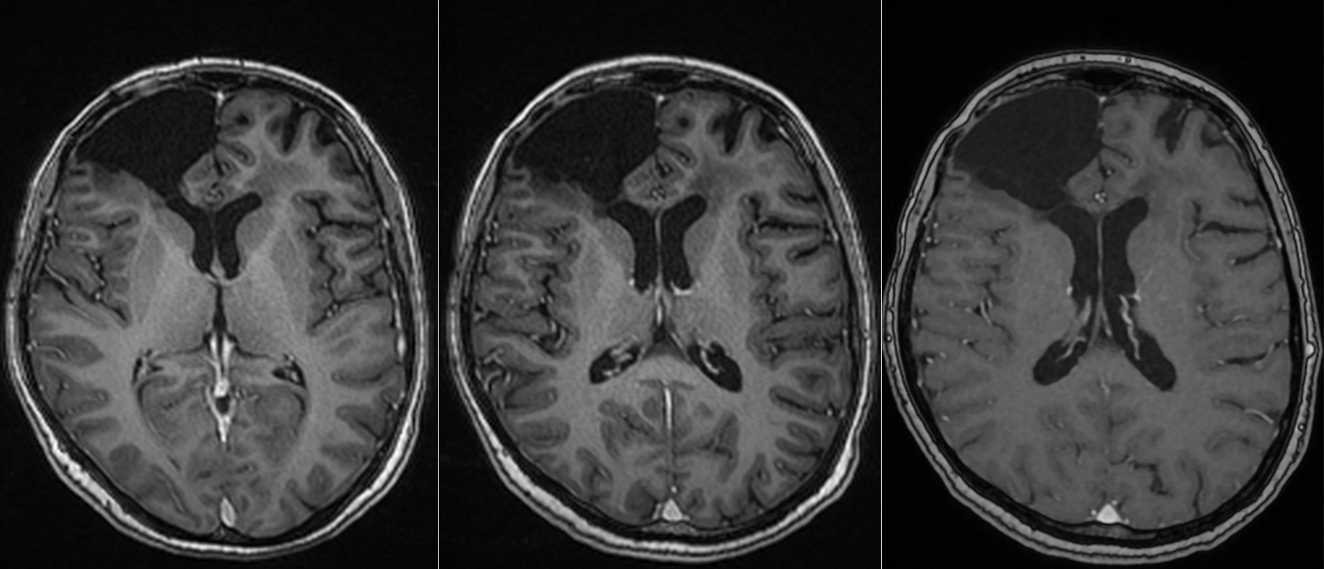

Se reface imagistica – de aceasta dată RMN cerebral cu contrast – și se constată prezența unei tumori cerebrale infiltrative de cca 7/7/6 cm, în cea mai mare parte negadolinofila, hipo-T1, hiper-T2 și FLAIR, cu zone hemoragice la interior și efect de masă important – deplasarea structurilor liniei mediene cu 2 cm, hernie de girus cinguli și hidrocefalie internă prin obstrucția formen Monro – imagine sugestivă pentru un gliom de grad înalt, cel mai probabil glioblastom.